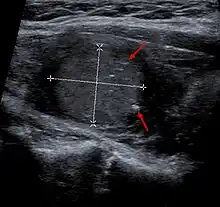

Medullary thyroid carcinoma on ultrasound with typical small calcifications (arrows)

Diagnosis is primarily performed via fine needle aspiration of the lesion of the thyroid to distinguish it from other types of thyroid lesions.[6] Microscopic examination will show an amyloid stroma with hyperplasia of parafollicular cells.